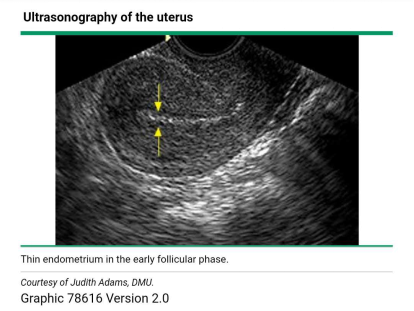

我们常常是用超声来检测月经周期中子宫内膜厚度及质地的变化,具体的测量方法是通过在矢状面的最大前后径水平,对子宫内膜与子宫肌层交界处的回声生成界面,进行测量而获得的厚度。不同时期,B超下看到的子宫内膜的厚度影像也不同。卵泡期月经过后,由于功能层脱落,这样一个时间段子宫内膜厚度就会变得很薄,一般4-5mm。

超声下表现为薄的强回声线。